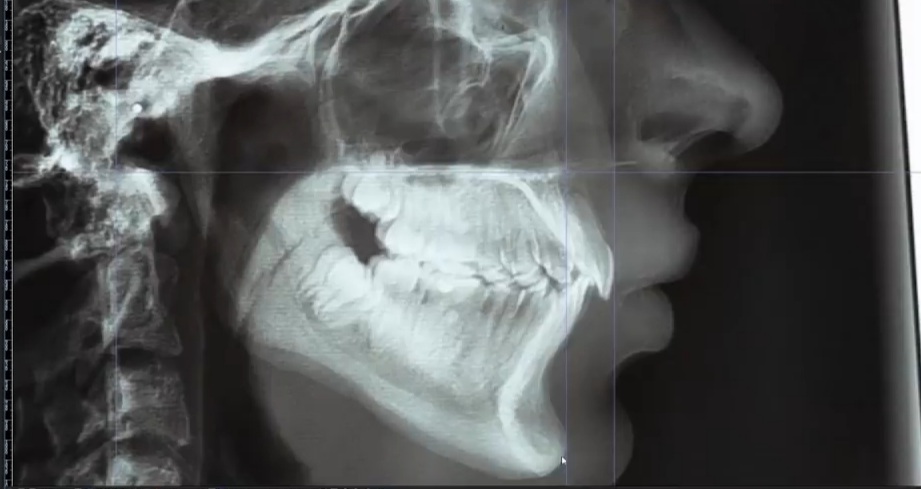

These are the forces acting upon the maxilla when the molars are gently touching:

Upwards force on the back only. There will be a CW rotation and this is definitely what you don't want.